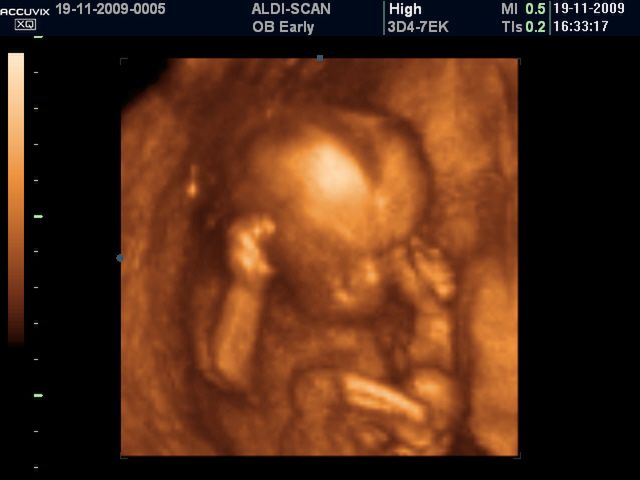

/ 3Płód w 11 tygodniu ciąży - rozmiary

Długość płodu to 5 centymetrów, waga 8 gramów